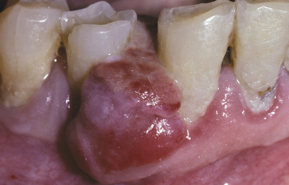

peripheral giant cell granuloma

notice the bluish color